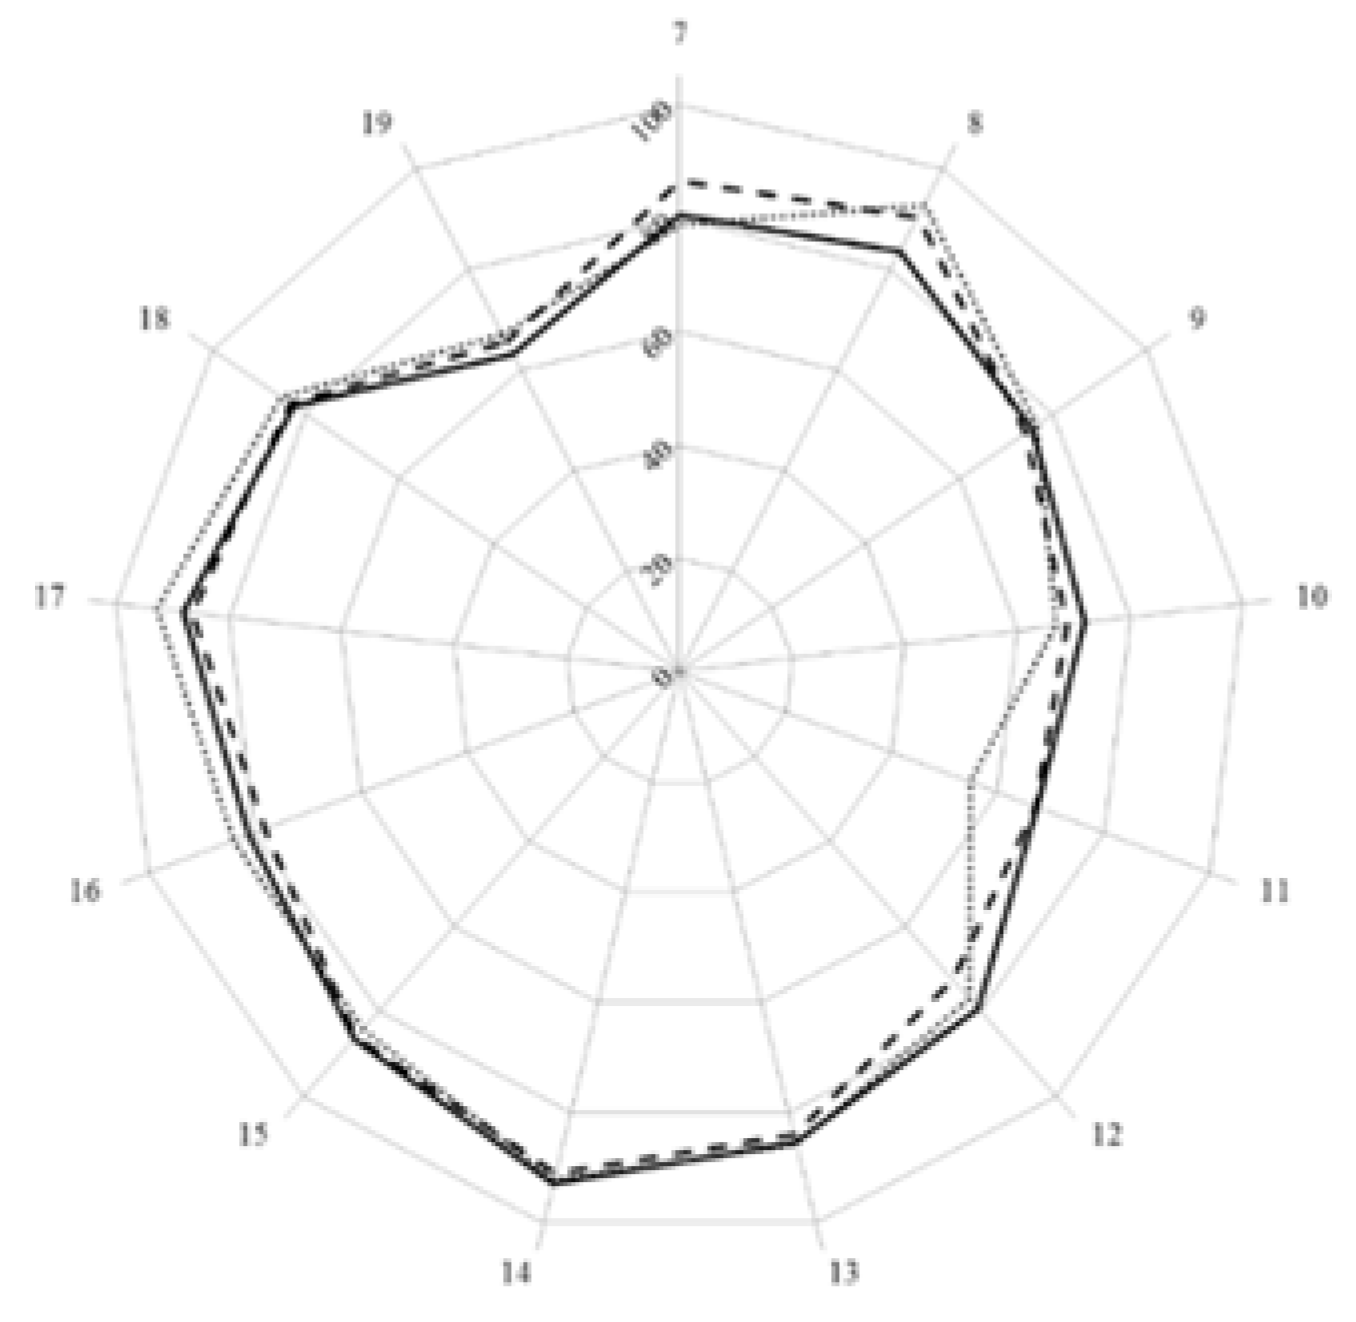

3. Results and Discussion

| Score (%) | 77.4 | 78.3 | 77.9 | |||

| Leik ordinal consensus | 0.59 | 0.55 | 0.58 | |||

| Cluster 7. Personal competences: learning and knowledge. | 1 | Ability to identify learning needs and to learn independently (including continuous professional development (CPD)). | 84.5 | 93.7 | 15.7 | 89.8 | 13.1 |

| 2 | Analysis: ability to apply logic to problem solving, evaluating pros and cons and following up on the solution found. | 88.8 | 94.5 | 7.5 | 91.1 | 3.6 | |

| 3 | Synthesis: capacity to gather and critically appraise relevant knowledge and to summarise the key points. | 85.1 | 92.8 | 10.8 | 87.9 | 4.0 | |

| 4 | Capacity to evaluate scientific data in line with current scientific and technological knowledge. | 76.5 | 87.3 | 18.5 | 75.8 | 0.4 | |

| 5 | Ability to interpret preclinical and clinical evidence-based medical science and apply the knowledge to pharmaceutical practice. | 86.0 | 81.2 | 5.2 | 75.9 | 17.3 | |

| 6 | Ability to design and conduct research using appropriate methodology. | 60.6 | 65.4 | 4.9 | 40.2 | 34.3 | |

| 7 | Ability to maintain current knowledge of relevant legislation and codes of pharmacy practice. | 81.7 | 86.3 | 3.3 | 91.7 | 25.7 | |

| Cluster 8. Personal competences: values. | 8 | Demonstrate a professional approach to tasks and human relations. | 86.6 | 91.5 | 7.7 | 94.5 | 23.3 |

| 9 | Demonstrate the ability to maintain confidentiality. | 85.4 | 92.3 | 22.8 | 95.3 | 50.6 | |

| 10 | Take full personal responsibility for patient care and other aspects of one’s practice. | 84.4 | 88.3 | 3.2 | 94.8 | 24.9 | |

| 11 | Inspire the confidence of others in one’s actions and advice. | 77.8 | 83.8 | 8.9 | 88.8 | 13.0 | |

| 12 | Demonstrate high ethical standards. | 85.3 | 95.3 | 43.4 | 95.2 | 24.6 | |

| Cluster 9. Personal competences: communication and organisational skills. | 13 | Effective communication skills (both orally and written). | 91.2 | 93.5 | 3.9 | 94.8 | 4.0 |

| 14 | Effective use of information technology. | 81.1 | 83.8 | 1.4 | 86.1 | 3.8 | |

| 15 | Ability to work effectively as part of a tea. | 86.4 | 83.3 | 6.1 | 89.2 | 1.1 | |

| 16 | Ability to identify and implement legal and professional requirements relating to employment (e.g., for pharmacy technicians) and to safety in the workplace. | 74.8 | 77.9 | 1.9 | 81.0 | 4.5 | |

| 17 | Ability to contribute to the learning and training of staff. | 73.5 | 79.6 | 6.6 | 82.5 | 6.6 | |

| 18 | Ability to design and manage the development processes in the production of medicines. | 61.2 | 60.0 | 0.8 | 43.2 | 38.0 | |

| 19 | Ability to identify and manage risk and quality of service issues. | 77.5 | 76.1 | 4.0 | 79.2 | 2.3 | |